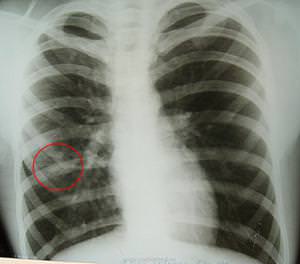

- Рентгенологическое исследование легких. Позволяет выявить заболевание на начальных этапах и провести дифференциальную диагностику, например, с раком легкого, имеющим сходную симптоматику. Главным признаком пневмофиброза является усиление и деформация легочного рисунка, расширение сосудистого пучка и тени с неровными заостренными контурами. Запущенный пневмофиброз выглядит на снимке в виде «пчелиных сот», то есть видны полые и уплотненные участки, чередующиеся друг с другом или/и рубцовых деформаций корней легких (пневмофиброз прикорневой),